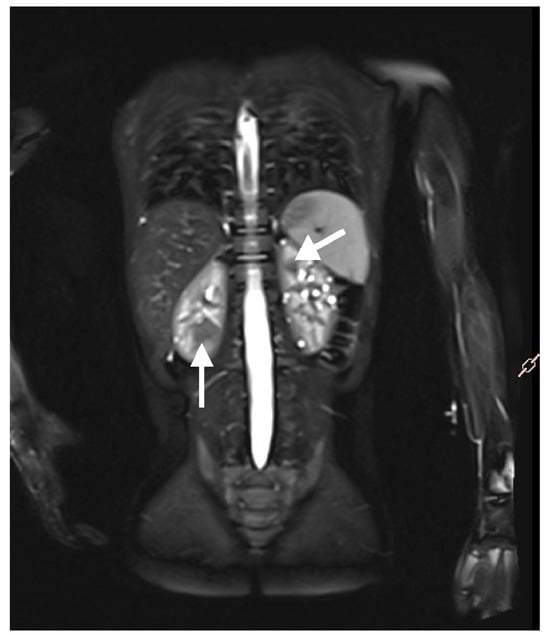

Magnetic resonance imaging (MRI) of the abdomen (Figure 5) and brain is the recommended imaging technique to diagnose and follow-up TSC-related kidney lesions. It remains the preferred method for evaluating AMLs, as 25–30% of them are fat-poor and are frequently overlooked in standard abdominal ultrasound examinations [6,49,50]. Additionally, MRI is highly effective in detecting other common abdominal abnormalities associated with TSC, such as renal cysts, aortic aneurysms, extrarenal hamartomas in the liver, and neuroendocrine tumors in the pancreas and other abdominal organs [51]. All individuals suspected of having TSC, should undergo MRI assessment of the brain to evaluate for cortical and subcortical tubers, subependymal nodules (SENs), neuronal migrational defects, and subependymal giant cell astrocytomas (SEGAs) [6].

Figure 5. An MRI with contrast of a 5-year-old boy. Multiple solid focal lesions in both kidneys—atypical angiomyolipomas (arrows). Additionally, numerous small cysts within the parenchyma of both kidneys.

The primary advantages of MRI are its lack of ionizing radiation, and its ability to provide excellent soft tissue contrast, even without the use of contrast agents. Compared to US, MRI provides more precise measurements of lesions and other pathological findings, particularly in cases involving coalesced or irregularly shaped lesions [47]. However, MRI has certain limitations, including reduced availability and the lower spatial resolution compared to CT, which avoids artifacts caused by abdominal movements that blur contours of lesions and organs [47]. Due to its stressful and time-intensive nature, MRI often requineedsral anesthesia, particularly in certain patient groups, including children, individuals with claustrophobia, or other anxiety or mental disorders. To reduce the necessity for multiple anesthesia sessions to facilitate diagnostic evaluation, MRI of the brain and abdomen is recommended to be performed in coordination [6,44].

In certain cases, contrast-enhanced MRI using gadolinium contrast agents proves to be a valuable tool, offering improved definition of angiomyolipomas and aiding in the differential diagnosis between fat-poor angiomyolipomas and other renal tumors. While the spatial resolution of contrast-enhanced MRI remains inferior to that of CT, it is often used for patients with allergies to iodinated contrast agents or those with a glomerular filtration rate (GFR) between 30 and 45 mL/min/1.73 m2 [47].